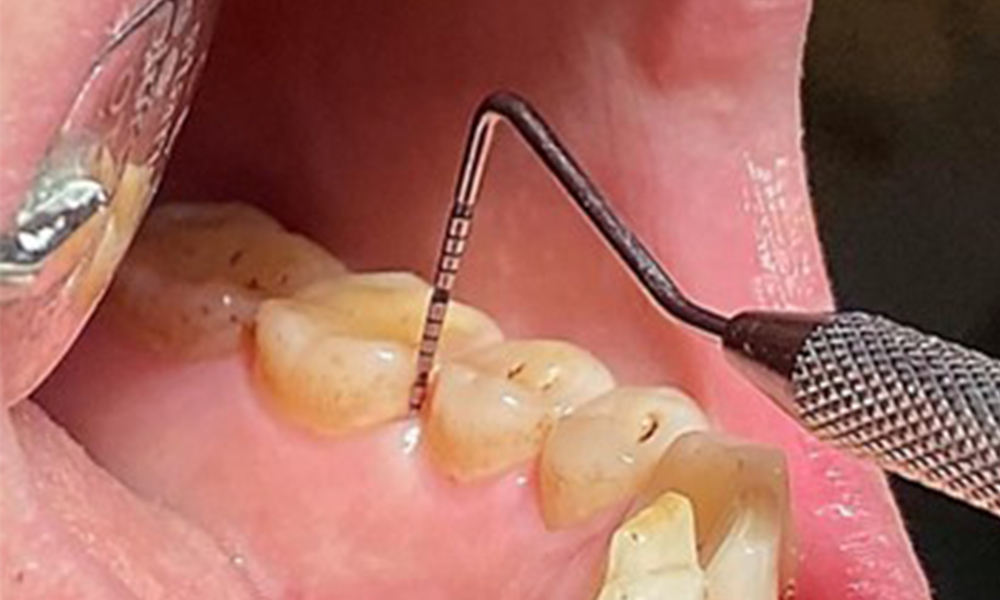

În contextul stării clinice generale favorabile, necesarul de măsuri individuale, ce urmează a fi determinat în cursul examinării intraorale, va avea un rol deosebit de important în planul de tratament. Va fi esențială determinarea periodică a profunzimilor de sondare. Sângerarea gingivală se diminuează la fumători, motiv pentru care diagnosticul clinic de parodontoză nu poate fi pus decât prin sondare (fig. 7). Punerea accentului exclusiv pe determinarea indicilor de sângerare poate masca prezența bolii parodontale și/sau a gingivitei existente. (5)